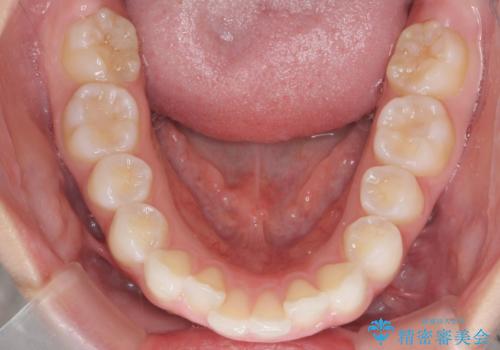

前歯のがたつき気になる。インビザラインモデレート

- 前歯のがたつきが気になるとの事で来院。

噛み合わせを確認したところ上の歯が全体的に前にある状態でした。

患者様は2のプランを選ばれたのでインビザラインモデレートで治療を行いました。

ガタつきがなくなり満足して頂けました。